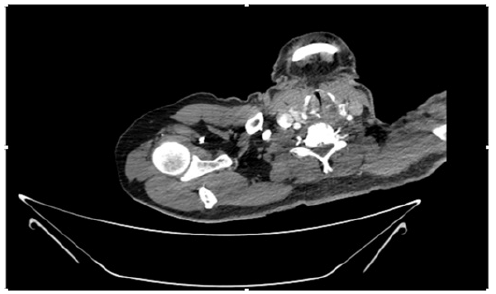

55-years-old chronic smoker had acute, severe pain in the right upper limb for one week; it was cold upto mid arm with skin discoloration. He also noticed numbness and weakness of movement of elbow joint. He underwent below elbow amputation in February 2023 for acute ischemia of left upper limb. He was a current chronic smoker; 15 pack year. General condition was weak; temperature was normal; blood pressure was 100/60mmHg; heart rate was 92/minutes with sinus rhythm; SpO2 was 97% on air; heart was normal. In lower extremities, all peripheral pulses were intact. Local Examination of right upper limb revealed as follows: tenderness; coldness; discoloration; decreased motor function and sensory modalities. Axillary, brachial and radial pulses were not palpable. Hand-held Doppler failed to detect any signal in arterial system; therefore, we arranged for emergency embolectomy. complete occlusion of right upper limb arterial system Full blood count showed high hemoglobin (14.6gm%); normal total WBC and platelet count. Coagulation profile was normal. Parenteral unfractionated heparin, antibiotics, tramadol, proton-pump inhibitors, anti-platelets and HMG CoA reductase inhibitors were given. Doppler ultrasound demonstrated complete occlusion of right upper limb arterial system. CT Angiogram illustrated occlusion of subclavian artery downwards on both sides. Figures 1-14 shows complete occlusion of right subclavian artery without collaterals. On Day ‘2’ of admission, the patient passed black tarry stool for 3 times. However, the vital signs were stable; blood pressure was 100/60mmHg; heart rate was 92/min; SpO2 was 97% on air; the abdomen was soft and not tender. Above elbow amputation was done on Day ‘2’ of admission. Intra-operative findings were as follows: (1) no active bleeding at brachial artery; (2) thrombosis along brachial artery; (3) muscle color and consistency were not healthy.

Figure 4: CT Angiogram at neck showing normal brachio-cephalic trunk, common carotid artery, and narrow right subclavian artery.

Figure 5: CT Angiogram at neck showing normal brachio-cephalic trunk, common carotid artery, and narrow right subclavian artery.

Figure 6: CT Angiogram at neck showing brachio-cephalic trunk, common carotid artery and narrow right subclavian artery.

Figure 7: CT Angiogram at neck showing brachio-cephalic trunk, common carotid artery and narrow right subclavian artery.

Figure 10: CT Angiogram at upper arm showing totally occluded right axillary artery; normal internal carotid artery and external carotid artery.